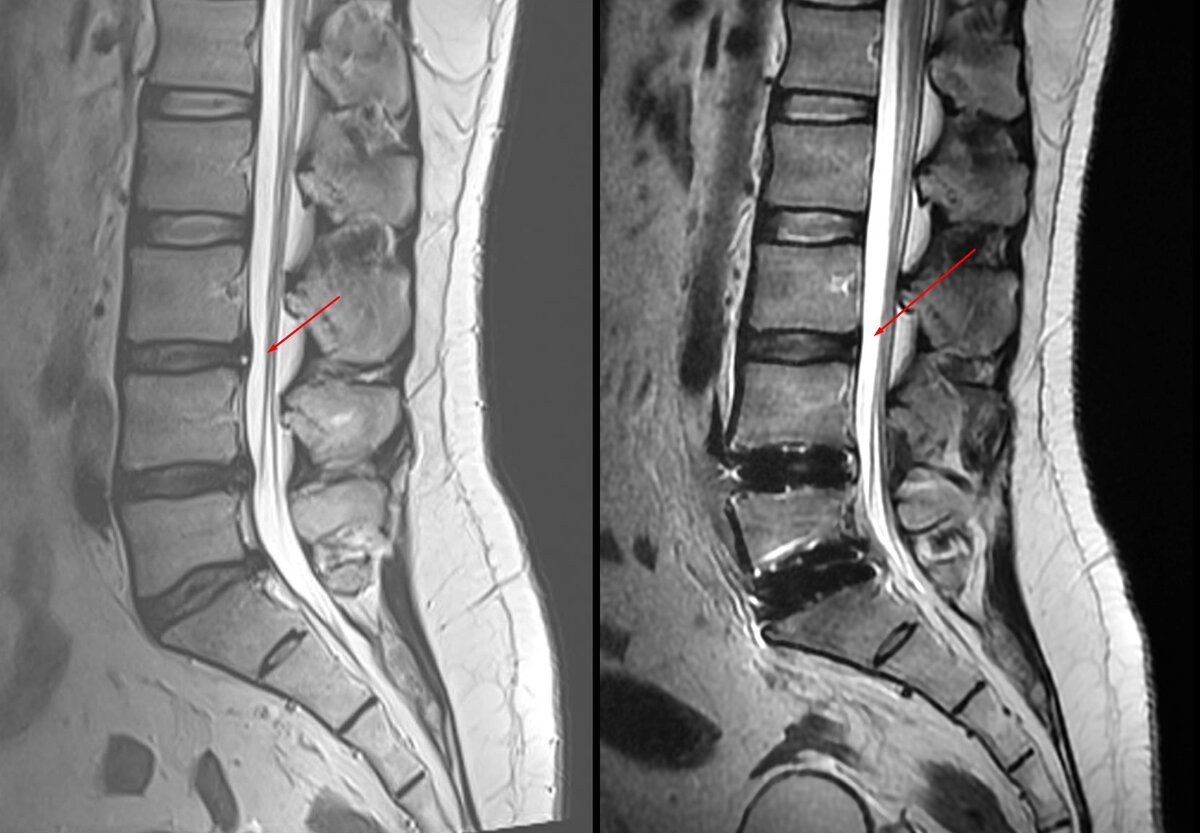

МРТ на 2ой день после операции. 2022г До и после. Более информативно будет через 3 месяца. Сейчас много отёков.